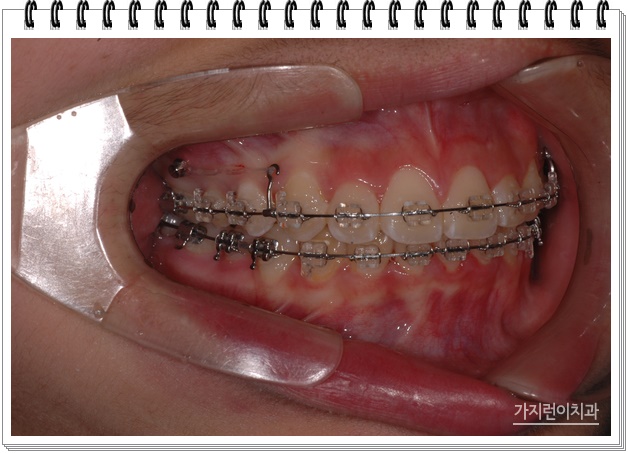

교정계획을 세우려면 엑스레이 촬영 후, 아래턱의 어금니 위치를 확인하게 됩니다. 이후 정확한 검진을 통해 플랜을 수립해야 했지만 성인과 달리 성장 중인 아이들의 경우에는 섣부른 발치를 할 수 없어 비발치 교정을 진행하는 편이 많습니다. 특히 주걱턱, 돌출입이 있는 경우에는 교정용 미니 스크류를 이용하게 되는데 (잇몸에 걸려 있는 고리 형태의 기구) 위 사진의 경유 상악 전체의 치열을 후방으로 이동시키는데 효과적인 히를 주기 위해 교정용 미니 스크류를 식립한 상태입니다. 이렇게 하면 상악골의 성장을 억제하면서 상악 어금니를 후방으로 당겨볼 수 있죠.